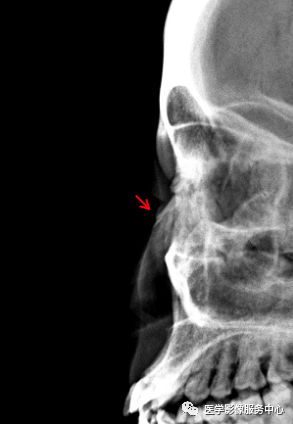

鼻骨

图片

两个病例均显示:鼻骨中远段骨质连续中断,断端向内下方移位。鼻骨骨折。

Warmreminder:鼻部受伤,有时鼻骨骨折不能做出诊断。小妙招鼻骨双侧位更容易观察。